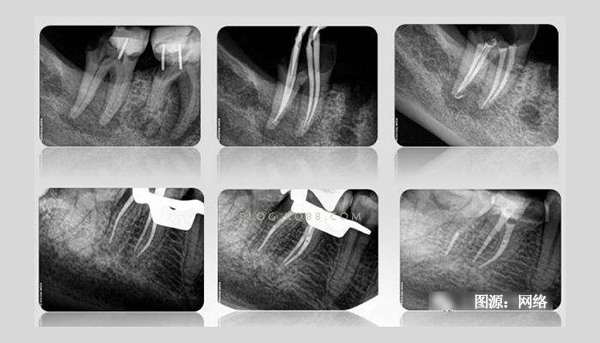

有根管治療史的患者都知道,在根管治療過程中需要反復(fù)拍攝多次X光片。一般說來,完成一顆牙的根管治療至少需要3張X光片:術(shù)前X光片、術(shù)中X光片、術(shù)后X光片。

術(shù)前X線片反映患牙及牙周組織的客觀情況—根管長(zhǎng)度、根尖周牙槽骨密度等,目的主要是幫助牙醫(yī)了解患牙的病變范圍、牙根情況、根管數(shù)目以及根尖周病變情況,根管是否存在鈣化,幫助醫(yī)生判斷患牙的預(yù)后以及根管治療的難度,是牙科治療的依據(jù)。

術(shù)中需要對(duì)根管預(yù)備情況進(jìn)行檢查,主要是輔助測(cè)量根管長(zhǎng)度,看根管預(yù)備是否到位,牙齒里面的神經(jīng)是否清理干凈。對(duì)于難度較大者需要一邊進(jìn)行根管預(yù)備一邊插針拍X線片,以監(jiān)測(cè)根管預(yù)備的方向和程度以求良好的治療效果。

術(shù)后X線片是為了觀察根管治療是否徹底,根管內(nèi)充填物是否合適,判斷根管治療充填的質(zhì)量是否到位。術(shù)后拍攝X線片,有助于醫(yī)生對(duì)治療效果的判斷,如果治療結(jié)果不滿意可及時(shí)更正,以免出現(xiàn)不必要的復(fù)診。根管治療術(shù)后拍X線片片已成為檢驗(yàn)根管治療質(zhì)量的手段之一,是根管治療規(guī)范化操作的一部分。